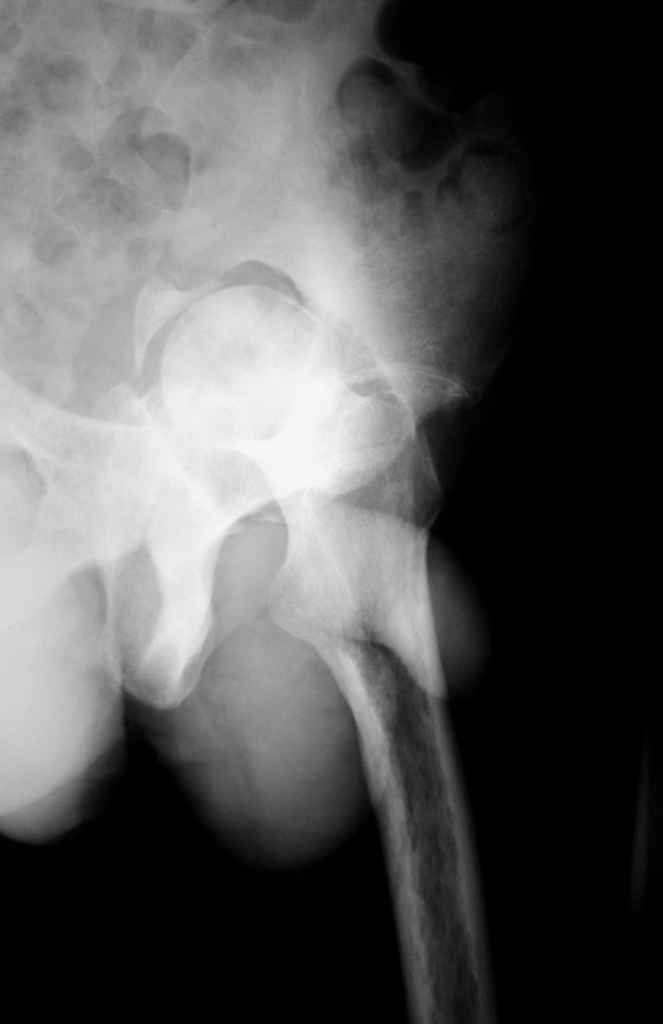

Еще одно наблюдение, неправильно сросшийся перелом заднего отдела ВВ с ввихом головки бедра 16-и летней давности.

С уважением, Р.Тихилов